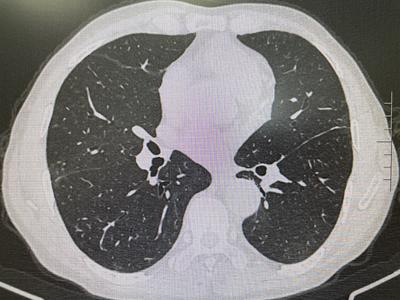

經近2年的門診規(guī)范化診療,病情完全得以控制并處于持續(xù)的穩(wěn)定狀態(tài)。近期復查肺部HRCT示間質性炎癥已完全吸收,肺功能檢測也基本正常,患者皮膚、肌肉、關節(jié)癥狀全部消除,現(xiàn)日常生活已恢復常態(tài),從事以前一樣的勞作。為此,老人及家屬充滿了感激之情。

(2021年12月 肺部HRCT)